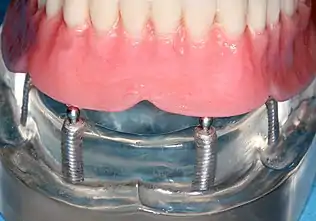

Four mandibular implants

Four lower implants to retain a complete denture with novaloc abutments

lower denture implant housing

Underside of a denture; housing fits like a ball and socket to hold the denture

When a removable denture is worn, retainers to hold the denture in place can be either custom made or "off-the-shelf" (stock) abutments. When custom retainers are used, four or more implant fixtures are placed and an impression of the implants is taken and a dental lab creates a custom metal bar with attachments to hold the denture in place. Significant retention can be created with multiple attachments and the use of semi-precision attachments (such as a small diameter pin that pushes through the denture and into the bar) which allows for little or no movement in the denture, but it remains removable.[17]:33–34 However, the same four implants angled in such a way to distribute occlusal forces may be able to safely hold a fixed denture in place with comparable costs and number of procedures giving the denture wearer a fixed solution.[54]

Alternatively, stock abutments are used to retain dentures using a male-adapter attached to the implant and a female adapter in the denture. Two common types of adapters are the ball-and-socket style retainer and the button-style adapter. These types of stock abutments allow movement of the denture, but enough retention to improve the quality of life for denture wearers, compared to conventional dentures.[55] Regardless of the type of adapter, the female portion of the adapter that is housed in the denture will require periodic replacement, however the number and adapter type does not seem to affect patient satisfaction with the prosthetic for various removable alternatives.[56]